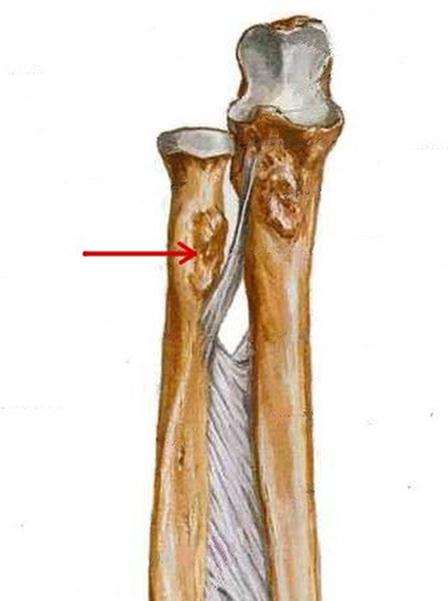

S: Стрелкауказывает на...

+:tuberositas radii